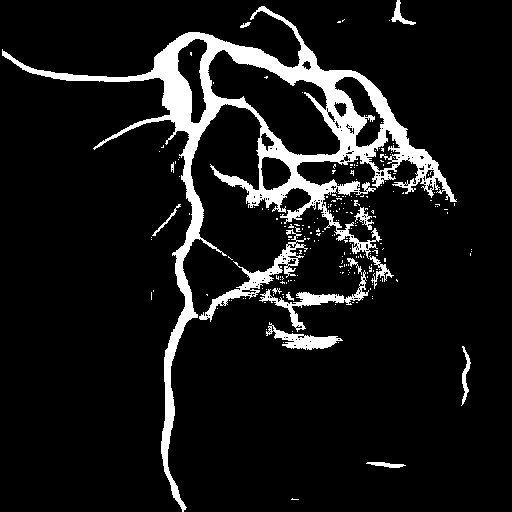

4.1 XACV Dataset

We collect 111 complete records of coronary artery X-ray videos, encompassing the injection, flow through the blood vessels around the heart, and dissipation of the contrast agent. Subsequently, we establish the XACV (X-ray Angiography Coronary Video) dataset. Each video consists of varying numbers of high-resolution coronary artery X-ray images. We invite experienced radiologists to annotate the vascular regions, focusing on one or two frames where the contrast agent is most prominent in each video. The XCAD dataset contains only a single image, and the CADICA video dataset does not provide corresponding ground truth. Therefore, in the following experiments, we conduct all the analyses on our collected XACV dataset and the corresponding GT for each sequence. In Figure 5, we show that compared to other publicly available datasets, XCAD [33] and CADICA [19], our dataset exhibits finer annotations in the vascular regions, providing an advantage for future related tasks. The development and use of our dataset have been approved by our institution’s IRB.